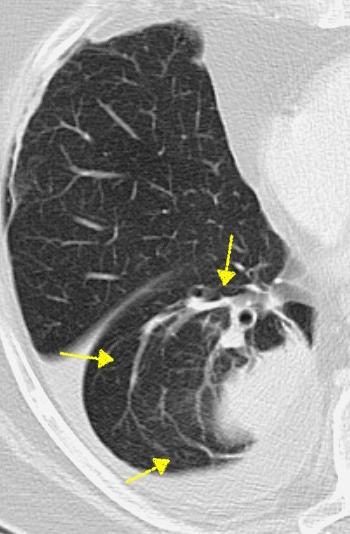

WINDEMERE” . SÍNDROME DE LADY

Forma indolente. Supresión de la tos. Língula y LM los más frecuentemente afectados. Bronquiectasias.

Coexistencia con nódulos centrilobulillares y patrón en mosaico muy sugerente.

Micobacteria atípica

Frecuencia en “clusters” familiares. Factores genéticos de sensibilidad del huésped a la infección pulmonar.

Colombo RE et al. Familial Clustering of Pulmonary Nontuberculous Mycobacterial Disease. Chest 2010./ Olivier KN. Lady Windermere Dissected: More Form Than Fastidious. Ann Am Thorac Soc. 2016/Martínez S et al. The many faces of pulmonary Nontuberculous Mycobacterial infection. AJR. 2007